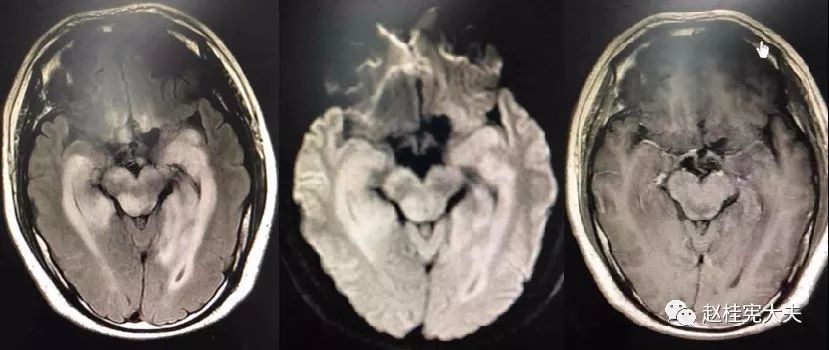

患者住院期间还请眼科会诊,除双眼玻璃体轻度浑浊,视力、视野、OCT均未见明显异常,未建议行玻切明确诊断。患者入院后嗜睡症状有加中,但一直未诉头痛,仅是头昏,静滴甘露醇症状减轻不明显。复查头颅磁共振平扫+增强:病灶范围较前明显扩大。轻度强化。